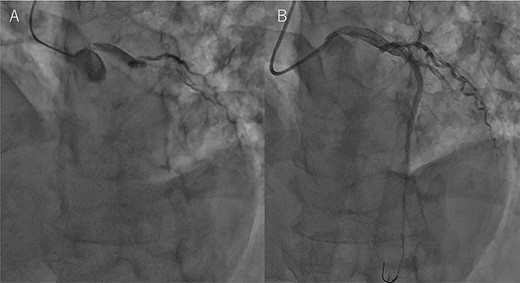

An Asian male in his 60s complained of sudden chest pain and was referred to a regional hospital. Electrocardiography showed massive ST-elevation in V1-4, and emergency coronary angiography revealed occlusion of the left anterior descending (LAD) artery (Fig. 1a). PCI was successfully performed (Fig. 1b), and IABP was inserted. Maximum value of creatine-kinase was 10 080 U/l, and his left ventricular function was severely impaired with an ejection fraction of 30%. High dosage of catecholamine was administrated and his hemodynamic status gradually recovered; however, he fell into profound cardiogenic shock on post PCI Day 6. Chest X-ray showed significant cardiomegaly (Fig. 2a), and trans-thoracic echocardiography revealed cardiac tamponade.

Coronary angiography findings. (A) Pre PCI, the LAD artery was completely occluded. (B) Post PCI, the LAD was recanalized.